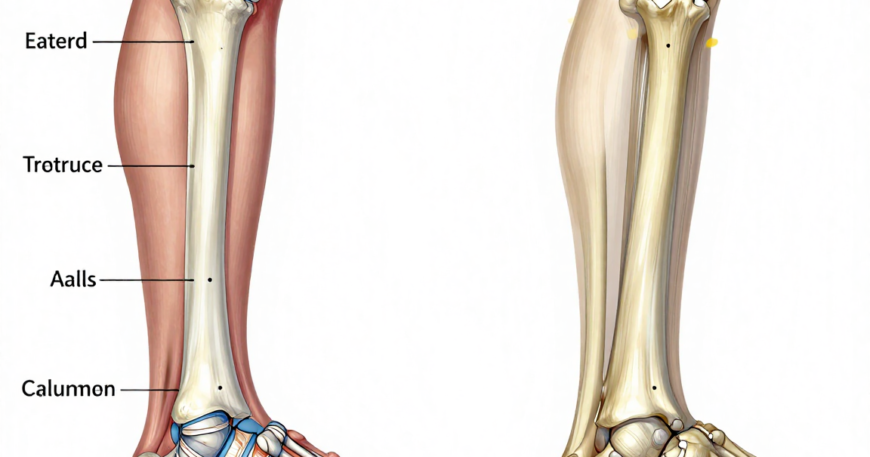

Many patients delay treatment after fractures, especially when pain seems manageable. However, untreated or improperly treated fractures can lead to malunion, chronic pain, deformity, and loss of function.

Early orthopaedic evaluation ensures proper alignment, stabilization, and healing. High-risk fractures, especially in elderly patients or accident victims, may require surgical fixation and ICU monitoring.